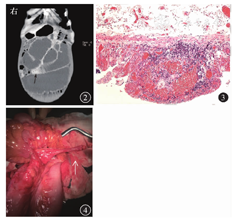

体温36.3 ℃,心率83次/min,呼吸18次/min,血压100/72 mmHg(1 mmHg=0.133 kPa),无力体型,腹膨隆,可见肠型和蠕动波,无压痛、反跳痛或肌紧张,肝脾触诊不大,肠鸣音4次/min,无气过水声。双下肢无水肿。入院后血常规检查示白细胞计数为5.78×109/L,中性粒细胞占比为0.56,血红蛋白为109 g/L(正细胞正色素性贫血),血小板计数为272×109/L。ESR为13 mm/1 h,CRP为0.72 mg/L。结核菌素试验、结核杆菌T细胞斑点试验(tuberculosis bacillus T cell spot test,T-SPOT.TB)、巨细胞病毒(cytomegalovirus,CMV)-IgM、CMV-PP65、CMV DNA、EB病毒DNA均为阴性。抗中性粒细胞胞质抗体、抗核抗体、癌胚抗原、CA125、CA19-9、LDH均未见异常。腹盆部增强CT检查和小肠重建(图2)示低位小肠梗阻,考虑梗阻部位位于回肠。2018年1月5日于全身麻醉下行肠粘连松解和小肠部分切除术,术中见回肠系膜侧畸形纤细肠管,手术病理(图3)检查示(畸形小肠)小肠黏膜显慢性炎,黏膜可见坏死,黏膜下层血管扩张充血,符合缺血性肠病表现。

予禁食水、静脉营养、置入胃管、通便等保守治疗后,患者腹痛、腹胀、肠型轻度缓解,经口进食后症状加重。考虑内科治疗疗效欠佳,经与患者及其家属充分沟通后,决定行手术治疗。遂于2018年1月5日在全身麻醉下行肠粘连松解和小肠部分切除术。术中见距回盲部约100 cm处小肠系膜侧畸形纤细肠管(图4),带动部分近端扩张小肠绕至升结肠后方,于十二指肠水平部下缘,自升结肠系膜和小肠系膜融合处钻出,粘连于脐下,导致肠梗阻。患者术后恢复良好并出院。